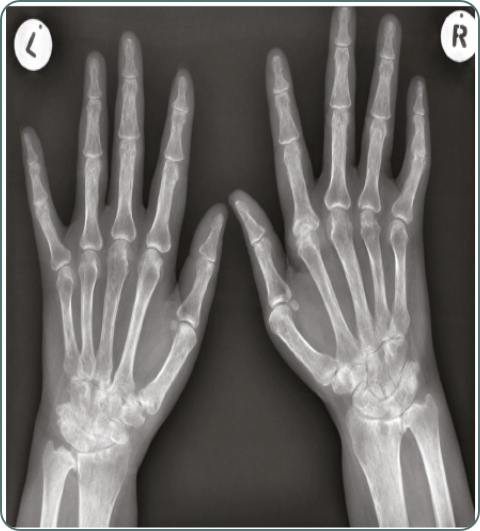

Joint X-rays

Imaging to evaluate joint damage, bone changes, and disease progression in various rheumatic conditions.